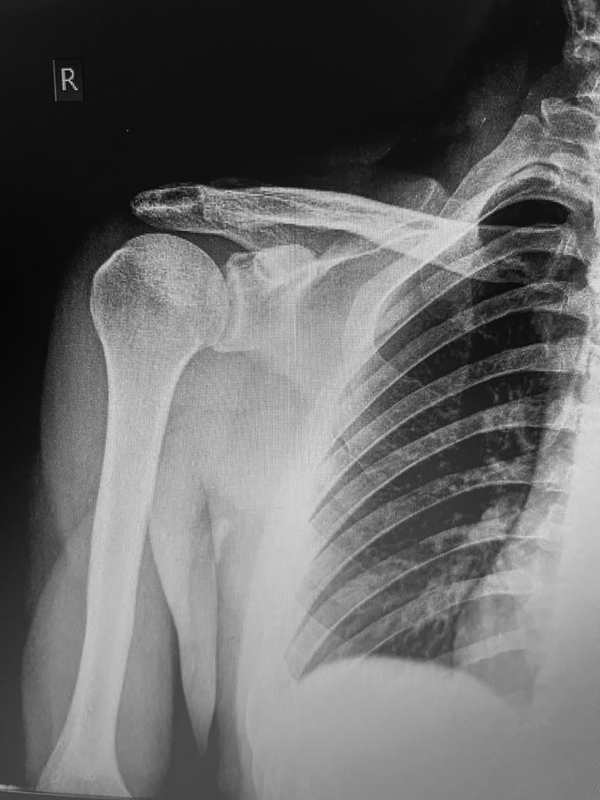

Posteriormente, se tunelizó el acromion de lateral a medial bajo visión fluoroscópica y se procedió al paso de un cabo de FiberTape® (Arthrex, Naples, Fl., EE. UU.) de medial a lateral, anudando y logrando estabilización acromioclavicular con sistema continuo de suspensión (fig. 3). Se exploró y reparó fascia deltotrapezoidal y se cerró por planos hasta piel.

Figura 3: Resultado postoperatorio de tenosuspensión coracoclavicular y cerclaje acromioclavicular por artroscopía.

En el postoperatorio se indicó inmovilización tipo cabestrillo por veintiún días y luego ejercicios pasivos hasta la sexta semana. Se aplicó escala Constant, con la que se obtuvo resultados excelentes por encima de los 80 puntos a los tres meses. No se presentaron complicaciones.